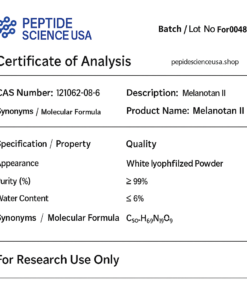

Adipotide (FTPP) COA CERTIFICATE